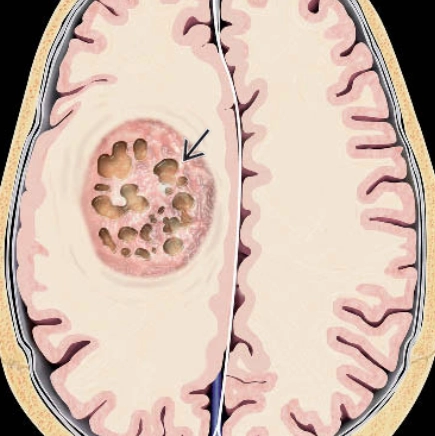

Di căn nhu mô não (Parenchymal metastases)